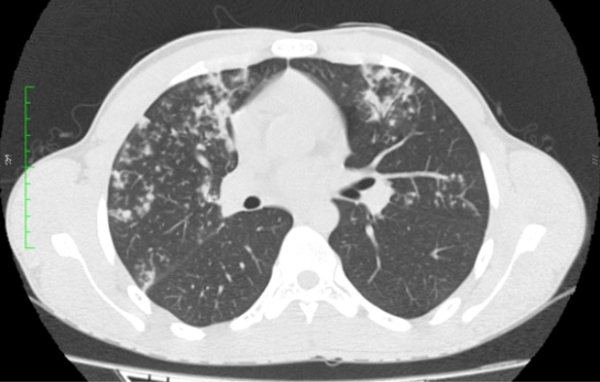

Paciente sexo masculino, 18 anos, sem comorbidades, com quadro arrastado de febre e perda ponderal há cerca de três meses. Foi realizado radiografia de tórax (não disponibilizada), com laudo inconclusivo. Optou-se por prosseguir investigação com tomografia computadorizada do tórax.

Diante das imagens, qual a melhor descrição e a principal hipótese diagnóstica?

CEscavação de paredes espessadas no lobo superior direito e nódulos com distribuição centrolobular dispersos pelo parênquima – tuberculose

DEscavação de paredes espessadas no lobo superior direito e nódulos com distribuição centrolobular dispersos pelo parênquima – aspergilose broncopulmonar alérgica